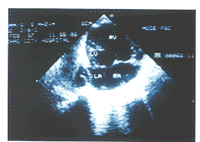

先心病组TR均有心内结构异常。其中:肺动脉狭窄3例,表现肺动脉瓣环或内径缩小,右房显著扩大,右室壁肥厚(图1)。左心发育不良综合征2例,表现左心房、室缩小,主动脉缩小,右心房、室及三尖瓣环扩大(图2)。完全型心内膜垫缺损1例,表现房间隔及室间隔上部缺失,心腔相互交通,房室瓣发育异常,形成左右心室共同房室瓣(图3)。

四腔观:左心房、左心室明显缩小

图2 左室发育不良综合征